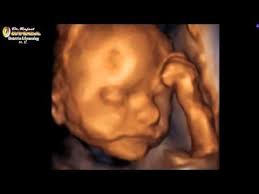

Sweet Baby Face 3d 4d Ultrasound

Sweet Baby Face 3d 4d Ultrasound. Book an appointment in Louisville or Elizabeth today. We Specialize in 4DHD Ultrasound 3D Ultrasound Photography and Baby Boutique items.

Sweet Baby Faces Ultrasound Studio. The entire scanning session video will be provided via email for unlimited sharing with friends and family. 1479 likes 26 talking about this 691 were here. Now you can see your baby up close and personal with a 3D4D HD ultrasound from Sweet Baby Face.